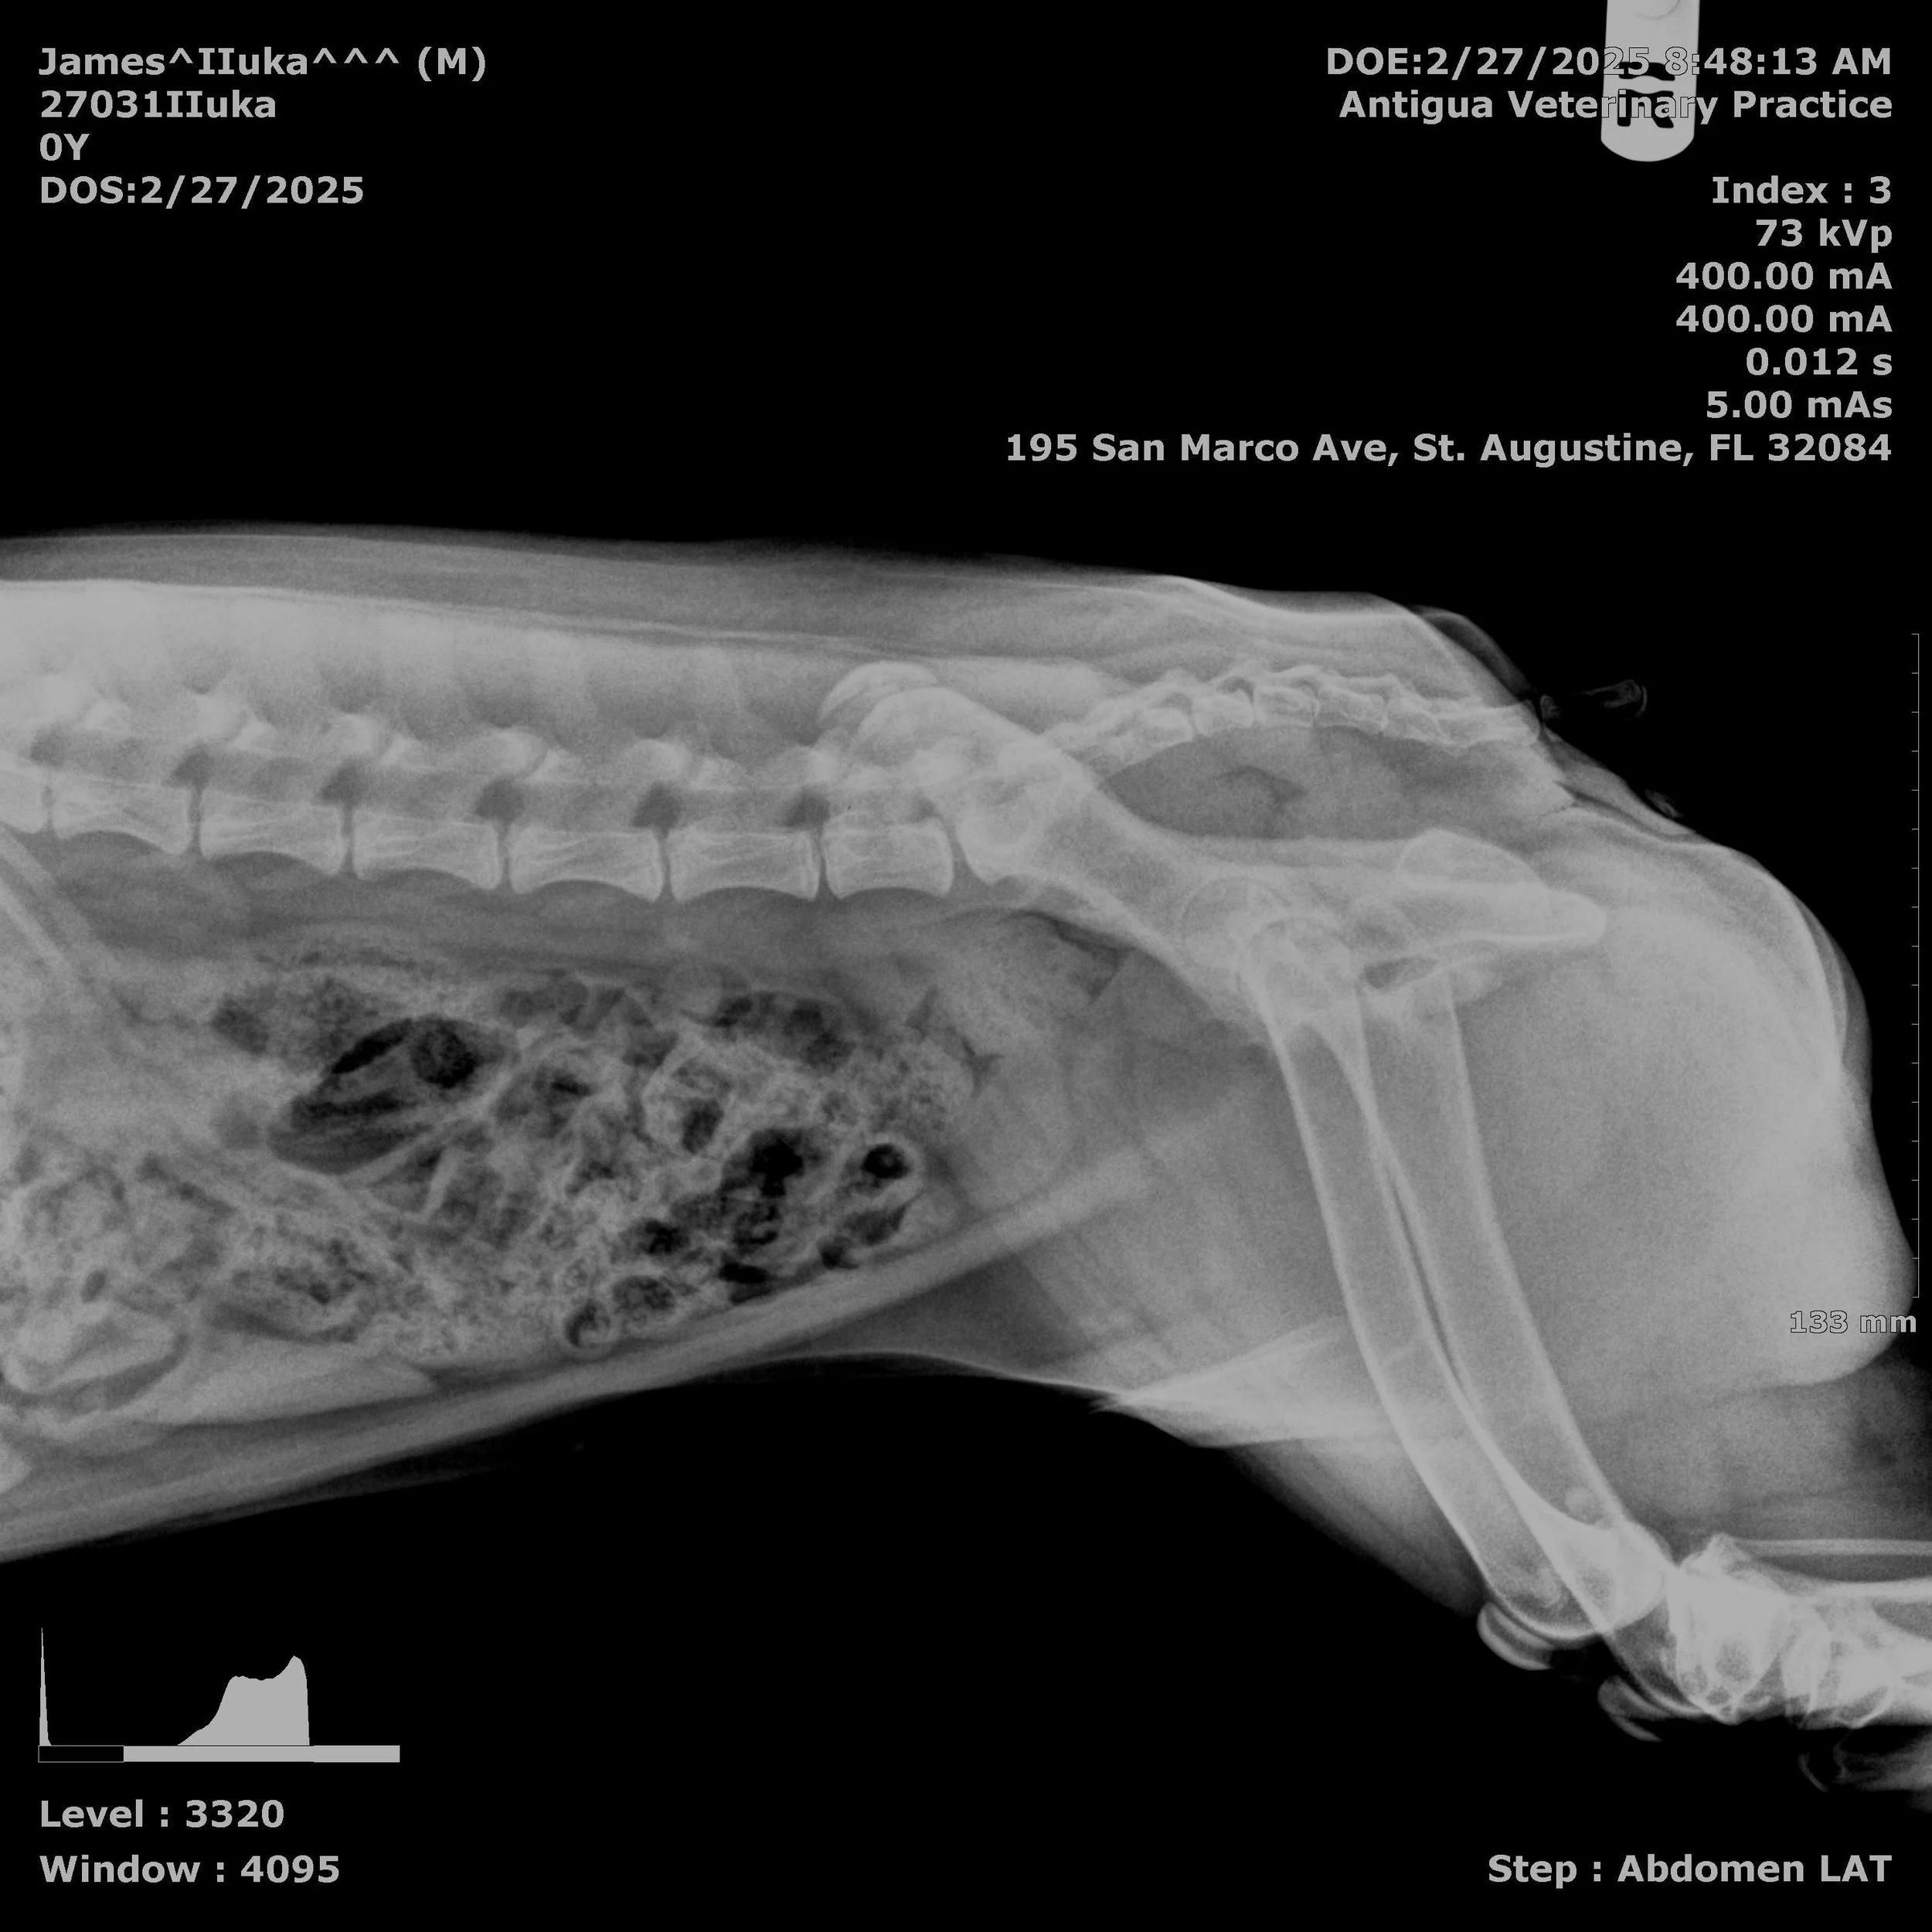

Veterinary Clinic Post-Op Xrays

The documentation reveals a troubling pattern of care failures following Iluka's routine surgery on August 12, 2025. Despite clear warning signs within 48 hours—including fever, loss of appetite, lethargy, abdominal pain, and vomiting—the follow-up care Iluka received was inadequate. His owners' growing concerns were repeatedly dismissed, basic diagnostic procedures were not performed, and critical hours were lost while his condition deteriorated.

Two independent veterinary expert's reviews concluded that the care involved "significant technical and communicative deficiencies" that directly contributed to septic peritonitis going undetected until it was too late. Iluka died on August 15, 2025, from preventable complications.